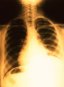

Отделение общей внутренней медицины предлагает программы

по оказанию первичной и вторичной медицинской помощи пациентам всех возрастов.

Углублённое исследование комплекса диагностических или терапевтических

вопросов, которые зачастую непросто подвести под то или иное конкретное

определение (Диагностическая клиника). Программы помогают исследовать и

лечить острые и хронические заболевания, а также вести долгосрочные наблюдения